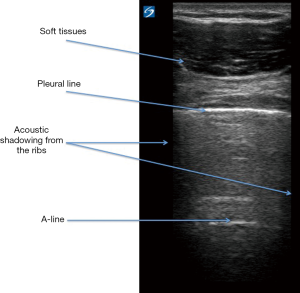

Before considering the lung POCUS features of PARDS, we will look at the normal lung POCUS. Full descriptions of how to scan the respiratory tract and use lung POCUS in pediatrics has been published elsewhere (2). Figure 3 summarises the key normal findings on lung POCUS. The authors’ experience is that using a high frequency linear probe provides very good image quality and depth. The use of a lower frequency curvi-linear probe maybe needed in larger children when further depth is required, but at the expense of image quality.

Start by identifying the Bat-wing sign, which is described because of the appearances of the upper and lower adjacent ribs producing ‘the wings of the bat’ with the pleural line forming the back (body) of the bat (2). The pleural line is a dense, crisp sharp white line, and should be seen shimmering and sliding back and forth to indicate normal movement of the pleura. The absence of pleural sliding suggests pathological processes, either because of lung under ventilation (e.g., collapse-consolidation, endobronchial intubation) or because of separation of the visceral and parietal pleura by air (i.e., a pneumothorax) (2). Pleural sliding, or indeed the absence of, can be confirmed by using the ‘motion mode’ (M-mode). This plots movement against time and allows movement of a given structure to be assessed; in lung POCUS this structure is the pleura. In M-mode, pleural sliding creates a seashore sign; the static muscle/soft tissue allows passage of the ultrasound which then hits the pleura, which if moving causes disruption of the ultrasound and therefore disrupts the M-mode trace (Figure 4) (2,11). Finally, the normal lung ultrasound will demonstrate A-lines, which are horizontal white lines and are artefact reflections of the pleural line, and therefore run in parallel to the pleural line (2) (Figure 3).